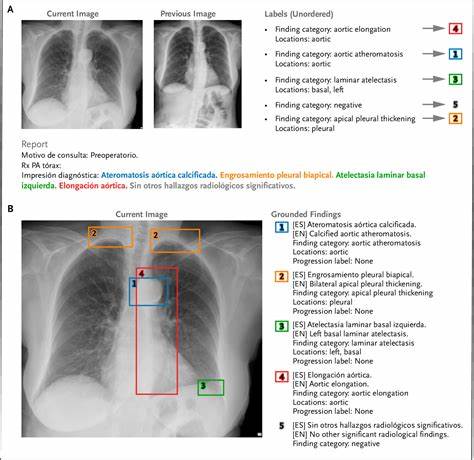

Рентгенологическая диагностика грудной клетки является одним из наиболее распространенных и важных методов медицинского обследования. С развитием искусственного интеллекта и машинного обучения в медицине возникает необходимость в высококачественных, обширных и хорошо аннотированных наборах данных, которые позволят совершенствовать автоматическую интерпретацию медицинских изображений. В этом контексте PadChest-GR представляет собой значимый шаг вперед, предлагая двуязычный и подробно разметанный эталон для радиологических отчетов, связанный с рентгенограммами грудной клетки. Уникальность PadChest-GR заключается в том, что он не только включает обширные визуальные данные, но и предоставляет полноценные, связные текстовые отчеты на двух языках — английском и испанском, что делает его ценным ресурсом для глобальных исследований и клинических приложений. PadChest-GR был разработан с учетом необходимости обеспечить точное и развернутое описание различных патологий, наблюдаемых на рентгеновских снимках грудной клетки.

Каждое изображение сопровождается детальным текстом, демонстрирующим глубину и комплексность радиологического анализа. Такой подход способствует созданию более надежных моделей искусственного интеллекта, способных автоматически генерировать медицинские отчеты с высоким уровнем точности и клинической информативности. Набор данных отличается возможностью генерации grounded radiology reports — то есть отчетов, основанных на точных локализациях патологических признаков на изображениях. Это дает возможность не просто классифицировать патологии, а подкреплять текстовые описания конкретными визуальными доказательствами, что является важным для повышения доверия и понимания результатов диагностики как среди врачей, так и среди пациентов. Кроме того, двуязычность PadChest-GR способствует расширению доступности и интероперабельности медицинской информации.

В эпоху глобализации и международного сотрудничества наличие данных на нескольких языках позволяет активнее привлекать исследователей из разных стран и способствует стандартизации медицинских описаний в радиологии. В техническом плане PadChest-GR включает тысячи рентгеновских снимков грудной клетки, каждый из которых аннотирован экспертами с использованием специализированных терминов, отражающих широкий спектр заболеваний и патологических состояний, таких как пневмония, плевральный выпот, сердечная недостаточность, узелковые образования и многие другие. Аннотации структурированы таким образом, чтобы не только идентифицировать наличие и тип патологии, но и обеспечивать локализацию и подробное описание. Такой детальный подход позволяет моделям машинного обучения лучше понимать взаимосвязь между визуальными признаками и медицинской терминологией. В последние годы разработки в области обработки естественного языка и компьютерного зрения сливаются для создания систем, которые могут одновременно анализировать изображения и формировать текстовые отчеты с высокой точностью.